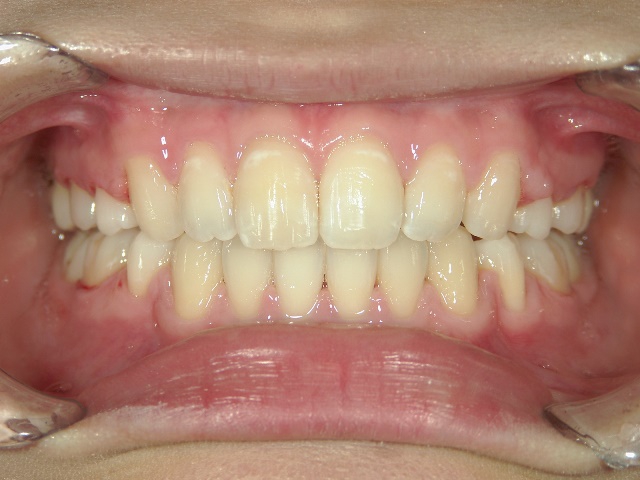

矯正歯科(全顎ワイヤー矯正)治療後

全顎ワイヤー矯正 症例(5)

20歳女性 浜松市東区

在住

治療期間2年4

ヶ月

矯正歯科 治療後